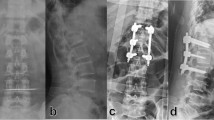

We observed a significant increase in high severity trauma (ISS > 16) patients between the pre-lockdown (2 (1.1%)) and the early lockdown period (7 (7.2%), p = 0.010), as well as between the pre-lockdown (2 (1.1%)) and the late lockdown (10 (8.3%), p = 0.002) (Fig. 3).

Stacked bar graph representation of high severity trauma (ISS > 16) according to the mechanism and the PL, L1, and L2 periods, with significant differences in the Fisher’s exact test. Others: L1: one assault, one work accident; L2: one sports accident, one work accident. PL: Pre-lockdown (from 02/18/20 to 03/16/20), L: Lockdown (from 03/17/20 to 05/11/20), L1: Early lockdown (from 03/17/2020 to 04/14/2020), L2: Late lockdown (from 04/14/2020 to 05/11/2020); ISS: International Severity Score.

In the last 4 weeks of the lockdown (L2) there was a 45.5% increase in weekly emergency department admissions compared to the early lockdown period (L1) (23.1 ± 6.0 vs. 33.6 ± 6.5, p < 0.001), there was also an increase in the weekly surgical procedures (24.2 ± 9.9 vs. 30.0 ± 3.2, p = 0.417). This may reflect the difficulty with maintaining strict confinement for a long time, with population behavioral fatigue related to these restrictive measures17. The improvement in the COVID-19 pandemic situation in France could also underlie this rebound in admissions, with a return to work for some activities. From a musculoskeletal injury point of view, the prolonged duration of confinement appeared to increase the occurrence of high severity trauma. The proportion of high severity trauma with an ISS > 16 requiring surgery increased drastically between the pre-lockdown (2 (1.1%)) and the early lockdown period (7 (7.8%), (p = 0.010)), with most of these being due to road traffic injuries, suicide attempts, and domestic accidents. This result was consistent with the late lockdown period (10 (8.3%))18,19. This phenomenon could be explained by behavioral changes due to confinement. Given the decrease in road traffic, one hypothesis is that unsafe driving behavior increased, thereby leading to more severe trauma. We also hypothesize that suicide attempts were more frequent in the late confinement period due to prolonged stress, isolation, and lack of psychiatric support17,18. Lastly, people spending time at home engaged in home improvements or do-it-yourself tasks that resulted in falls from ladders or roofs, as described by Park et al.9.